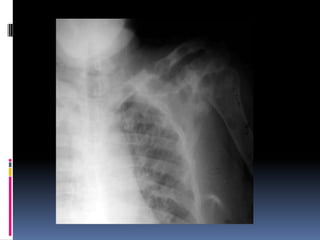

Look at  Softtissue  Bony cage

Soft tissue andbony structures  Check for  Symmetry  Deformities  Fractures  Masses  Calcifications  Lytic lesions